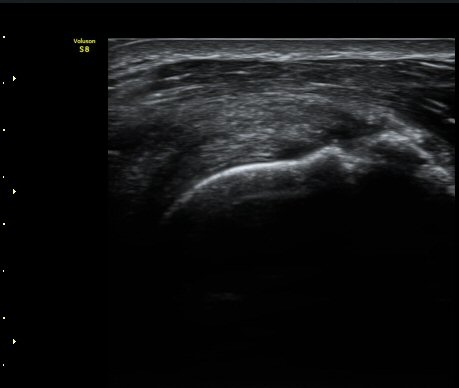

ÃÊÀ½ÆÄ °Ë»ç

ÀÌµÎ¹Ú±Ù°Ç È¾´Ü¸é°Ë»ç¿¡¼­ °ÇÁÖÀ§¿¡ ¼Ò·®ÀÇ ¼ö¾×Àú·ù¿Í Á¡¾×³¶³» ¾×Àú·ù°¡ °üÂûµÈ´Ù(»çÁø 1, 2).